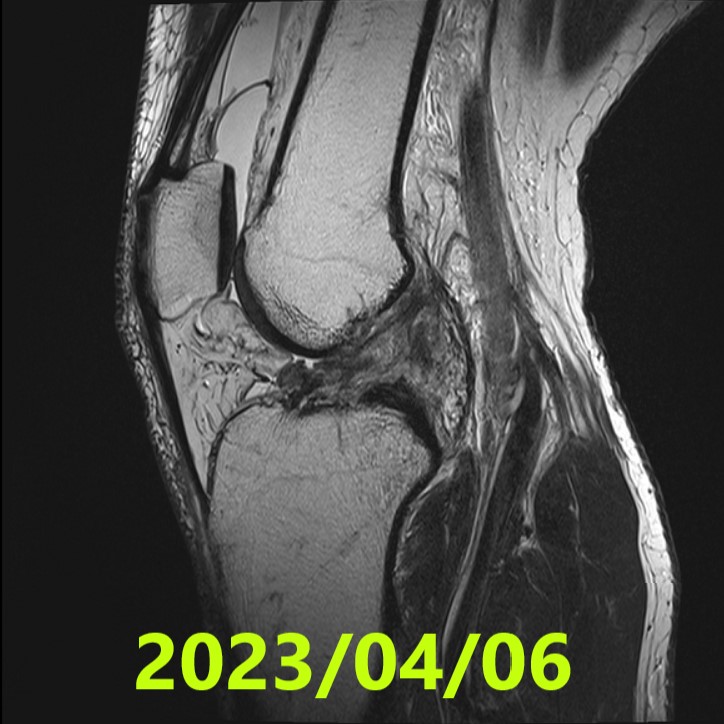

Initial Evaluation (MRI #1)

- Date: 6 April 2023

- Diagnosis: Left knee complete ACL rupture

- Ihara classification: IV (Grade 4) — Confirmed by consensus of 3 independent specialists

- MRI #1 (2023/04/06): Ihara IV — confirmed as severe complete rupture by 3 specialists